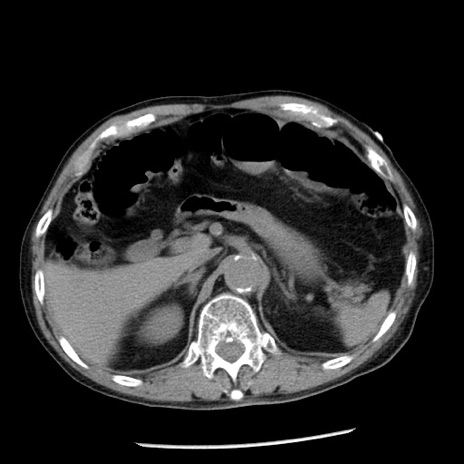

冠状断像

症例26(横断像)

【症例】80歳代男性

【主訴】嘔吐

【現病歴】昨晩2回嘔吐あり、今朝になっても嘔吐あり。来院。

【既往歴】胃潰瘍

【身体所見】意識清明、BT 37.6℃、BP 166/95mmHg、HR 100bpm、SpO2 97%、腹部:平坦・軟、腸蠕動音聴取良好、圧痛なし。

【データ】WBC 21900、CRP 1.46